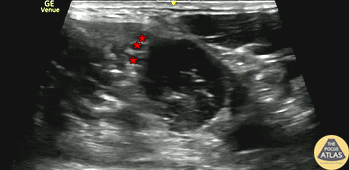

20s M with PMH recurrent shoulder dislocation presented with shoulder pain and concern for dislocation. Radiographs confirmed anterior glenohumeral dislocation and showed a Hill-Sachs deformity. An interscalene brachial plexus block was performed for analgesia. The block is shown here, with the needle entering from the lateral aspect or left of screen, injecting anesthetic adjacent to the nerve roots (*) within the interscalene groove. The patient had good pain control with the block, allowing easy bedside reduction without additional parenteral medications or conscious sedation. Repeat radiographs confirmed adequate reduction of the dislocation and the patient was discharged with orthopedic follow up. Dr. Molly Thiessen Denver Health Medical Center